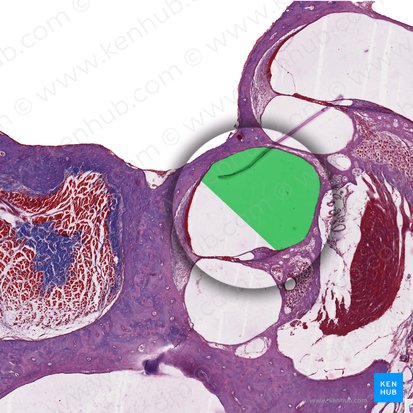

Overview of the bony and membranous structures of the labyrinth.

The cochlear duct divides the cochlear canal into three compartments: the scala media, the scala vestibuli, and the scala tympani. The scala vestibuli is the uppermost of these three chambers.

The scala vestibuli and scala tympani are both perilymph-filled structures, while the scala media is filled with endolymph.

The scala vestibuli meets the scala tympani at the apex called the helicotrema.